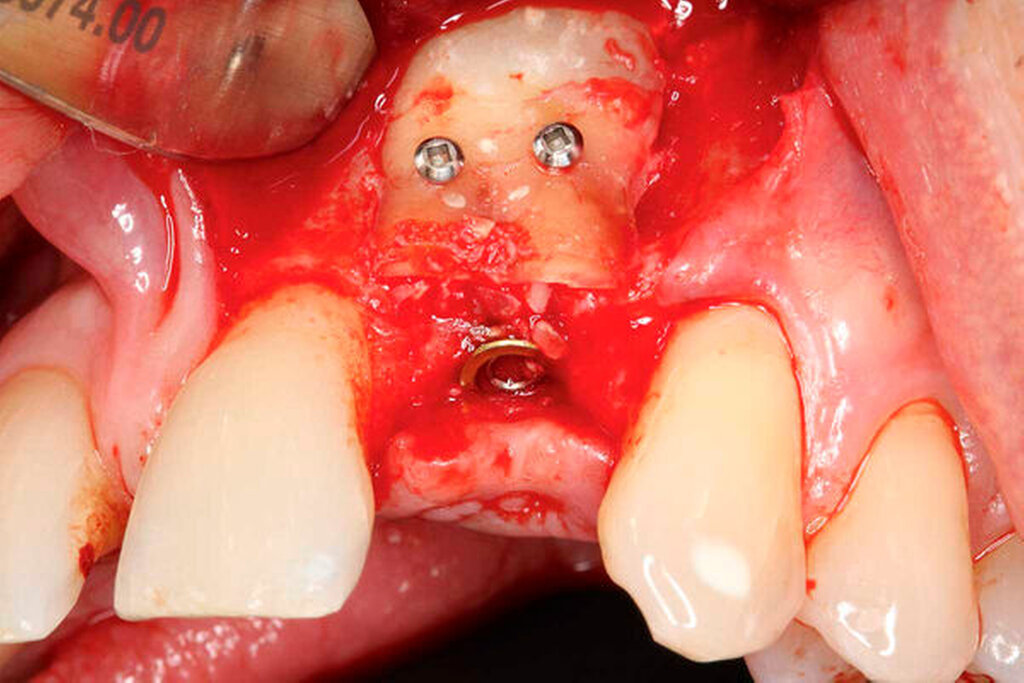

Nach Lappenbildung und Darstellung des Kieferkamms erfolgte die Aufbereitung des Implantatlagers gemäß Protokoll des Implantatherstellers. Anschließend wurde ein Implantat (ASTRA TECH Implant SystemTM EV, Dentsply Sirona, York, USA) inseriert (Abbildungen 3a bis 3c).

Die zuvor gewonnene und aufbereitete Dentinscheibe wurde mit Osteosyntheseschrauben (microscrews, Stoma, Emmingen-Liptingen, Deutschland) lateral des Defekts fixiert und das aufbereitete Dentinpartikulat in den Hohlraum zwischen Zahnscheibe und Implantat eingebracht (Abbildung 3d). Der Wundverschluss erfolgte spannungsfrei mit nichtresorbierbarem Nahtmaterial (Supramid 5/0, Serag-Wiessner, Naila, Deutschland). Postoperativ wurde ein DVT als Röntgenkontrolle angefertigt. Dieses zeigt das Implantat regio 22 in der Sagittalebene. Deutlich erkennbar ist die fixierte Zahnscheibe (Abbildung 4a).